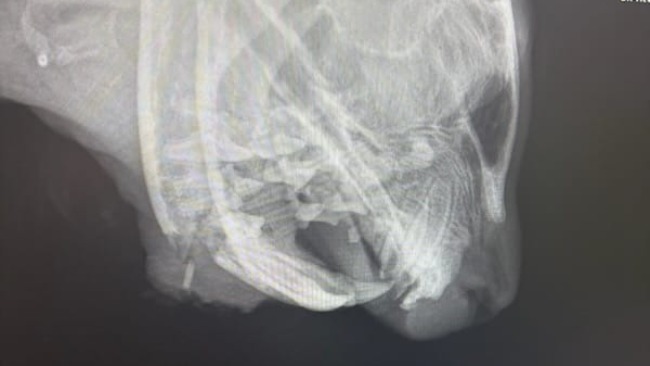

Lucjuszek jest po operacji łapki i po operacji szczęki, w której konieczna była częściowa amputacja. Miednica i ogonek są złamane i na ten moment leczone zachowawczo. To nie jest prosta rekonwalescencja. Dziś znów trafił do kliniki z powodu silnego bólu. Sytuacja jest dynamiczna, reagujemy na bieżąco.

Pojawił się lekki stan zapalny, od dziś ma włączony antybiotyk. Jest zabezpieczony przeciwbólowo. Każdy dzień to kontrola, obserwacja, decyzje podejmowane krok po kroku.